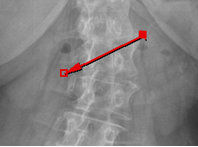

Distancia punto a punto sólo debe dar clic izquierdo sostenido, indique un punto a otro.